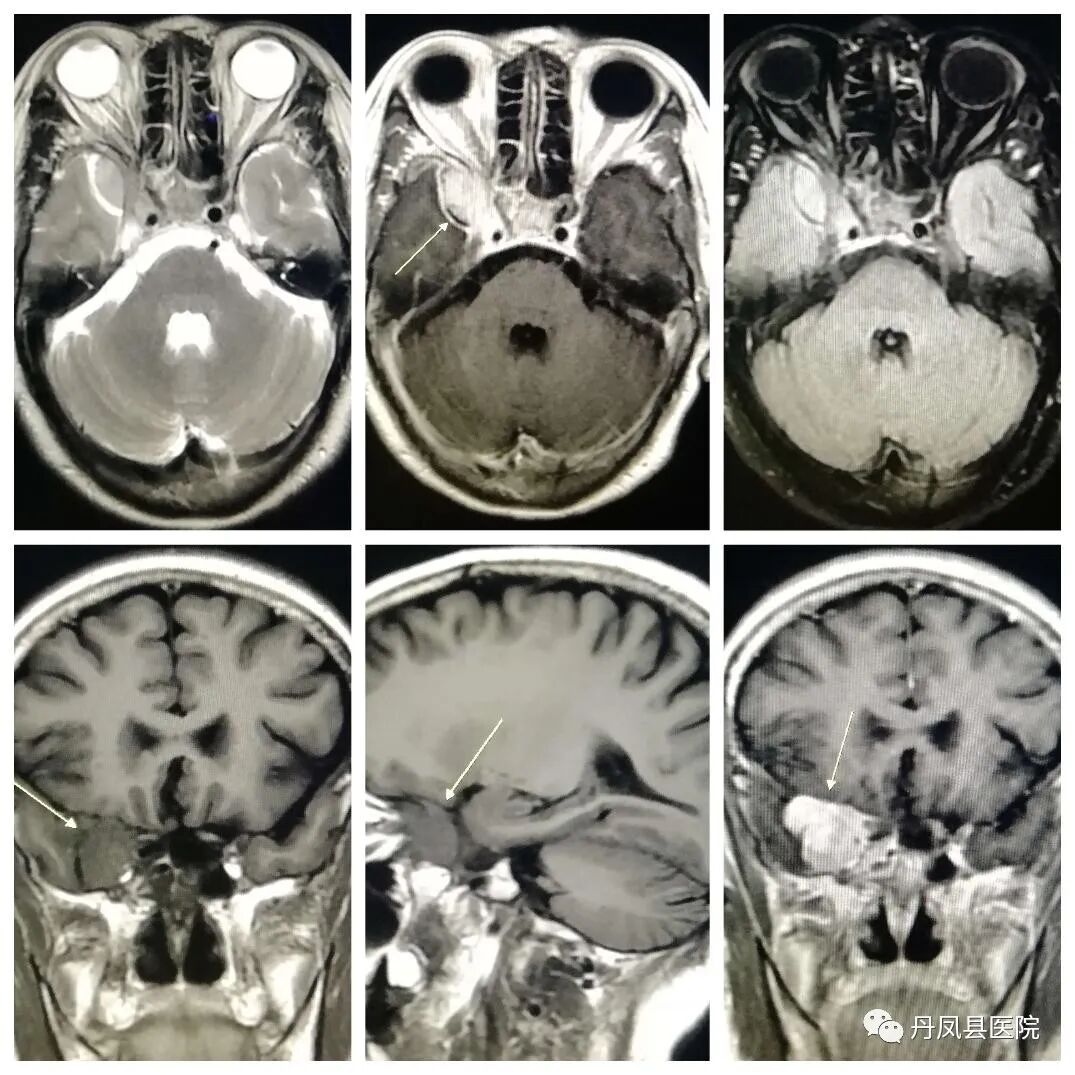

开展项目MRI磁共振设备是我县第一台检查设备,其扫描速度快、噪音低、图像分辨率高,能够进行全身各部位磁共振平扫、增强扫描及血管成像(MRA、MRV)、功能成像(DWI、DTI、SWI、MRS)、灌注成像、胰胆管水成像(MRCP)、泌尿系水成像(MRU)等检查。尤其在中枢神经系统、胆道系统、脊柱判断新旧骨折、骨转移瘤、早期股骨头缺血坏死、关节软骨损伤、韧带肌腱损伤有不可替代的优势,为临床提供更多、更丰富的影像诊断信息。磁共振的多方位、多参数、多轴倾斜断层对中枢神经系统病变的定位、定性诊断极其优越。中枢神经系统疾病的诊断中,除颅骨骨折和颅内急性出血不及CT外,在脑部肿瘤、颅内感染、脑血管病变、脑白质病变、脑发育畸形、脑退行性病变、脑室及蛛网膜下腔病变、脑挫伤、颅内亚急性血肿及脊髓的肿瘤、感染、血管性病变及外伤的诊断有明显优势。

![]()

急性脑梗死

脑膜瘤